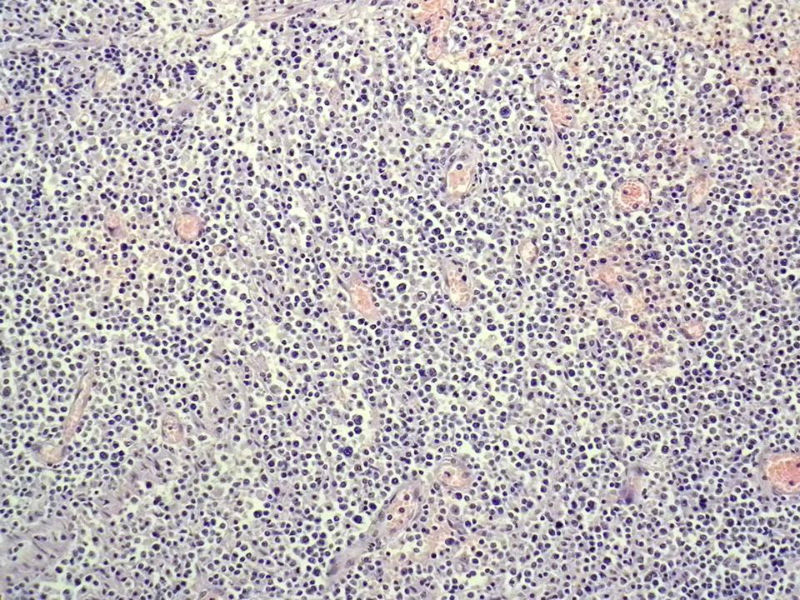

女,53岁,横结肠有9X6厘米大小溃疡,手术切除。

中老年人,溃疡很大,可见淋巴浆细胞样细胞弥漫浸润,散在大细胞,疑非霍奇颈淋巴瘤,倾向MALT伴浆样分化,不知是否破坏肌层?可否传肌层图?需IHC标记,鉴别淋巴瘤、腺癌及其它。

肉眼观仅是溃疡?有没有肠壁增厚、隆起?周围粘膜情况?肌层情况?有淋巴浆细胞样细胞、中心细胞,散在少量不成片的大细胞,不排除MALToma伴大细胞转化。

本例肉眼溃疡如溃疡性结肠炎,肠壁无明显增厚,表面辅以坏死,溃疡边缘稍隆起。镜下淋巴样细胞局限在粘膜层,肌层未见。谢谢!